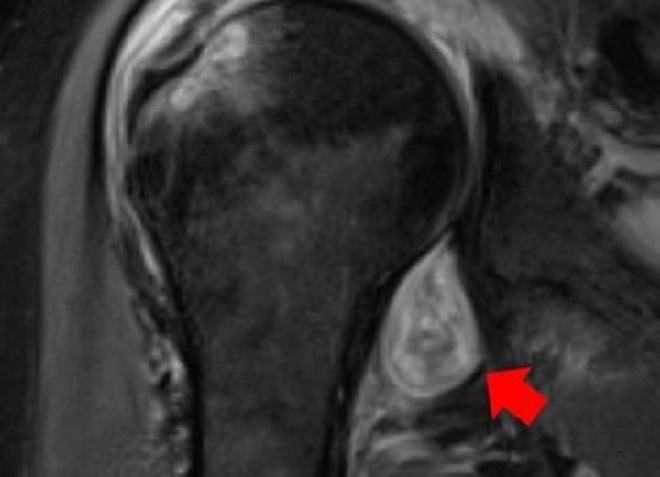

Hình ảnh MRI trên vai một bệnh nhân COVID-19. Mũi tên màu đỏ là vị trí viêm khớp. Sau khi nhiễm nCoV, bệnh nhân bị đau vai, viêm khớp dạng thấp kéo dài dù các triệu chứng khác đã hết.( Ảnh: Đại học Northwestern)

Tiến sĩ Swati Deshmukh, giảng viên tại Trường Y Feinberg, thuộc Đại học Northwestern, thành viên nhóm tác giả, cho biết: “Chúng tôi nhận ra virus SARS-CoV-2 có thể kích hoạt vật chủ tự tấn công theo những cách khác nhau. Điều này tiềm ẩn nguy cơ dẫn đến các vấn đề về khớp vĩnh viễn”.

Theo Eurekalert, bài báo của nhóm tác giả được công bố trên tạp chí Skeletal Radiology ngày 17/2. Trong đó, nghiên cứu đánh giá dữ liệu của bệnh nhân đến khám tại Bệnh viện Northwestern Memorial từ tháng 5/2020 đến 12/2020.

"Nhiều bệnh nhân bị rối loạn cơ xương liên quan COVID-19 sau khi hồi phục. Tuy nhiên, một số người có triệu chứng rất nặng, ảnh hưởng đến chất lượng sống. Họ buộc phải tìm kiếm chăm sóc y tế dù đã khỏi COVID-19”, tiến sĩ Deshmukh, giảng viên tại Trường Y Feinberg, thuộc Đại học Northwestern, cho biết thêm.

Theo vị chuyên gia này, hình ảnh CT, MRI, X-quang mà nhóm thu được cũng lý giải vì sao một người có triệu chứng đau cơ xương khớp kéo dài sau Covid-19. Trong một số trường hợp, bác sĩ X-quang có thể đề xuất chẩn đoán người mắc COVID-19 dựa trên những hình ảnh này, nhất là với trường hợp chưa thể sàng lọc họ có nhiễm virus hay chưa.